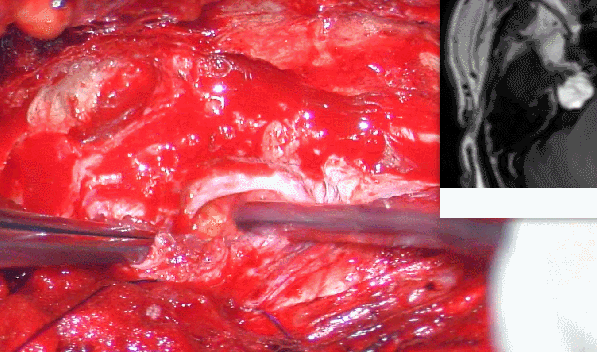

手术方案:1.解除右侧下颌神经骨性卡压;

2.肿瘤考虑为良性脂肪瘤,安全前提下尽力切除海绵窦-CPA区内占位;

3.肿瘤位于海绵窦内,卵圆孔-破裂孔区,为颅底孔道结构改变,采用前颞下经中颅窝入路,进入海绵窦区,术中避免损伤相关结构。